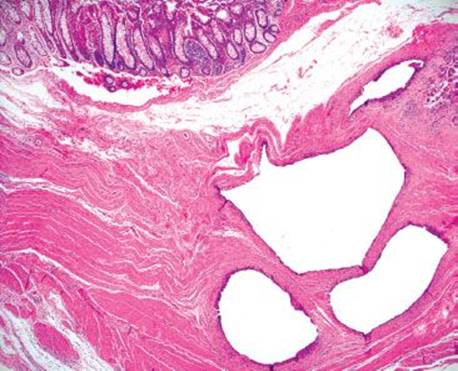

Figure 4.259 PCI. Histologic sections show multiple cyst-like spaces in the muscularis propria.

Figure 4.260 PCI. Alternate image, same patient.

Figure 4.261 PCI. Higher power shows that the cyst-like spaces are lined by histiocytes and foreign body giant cells.